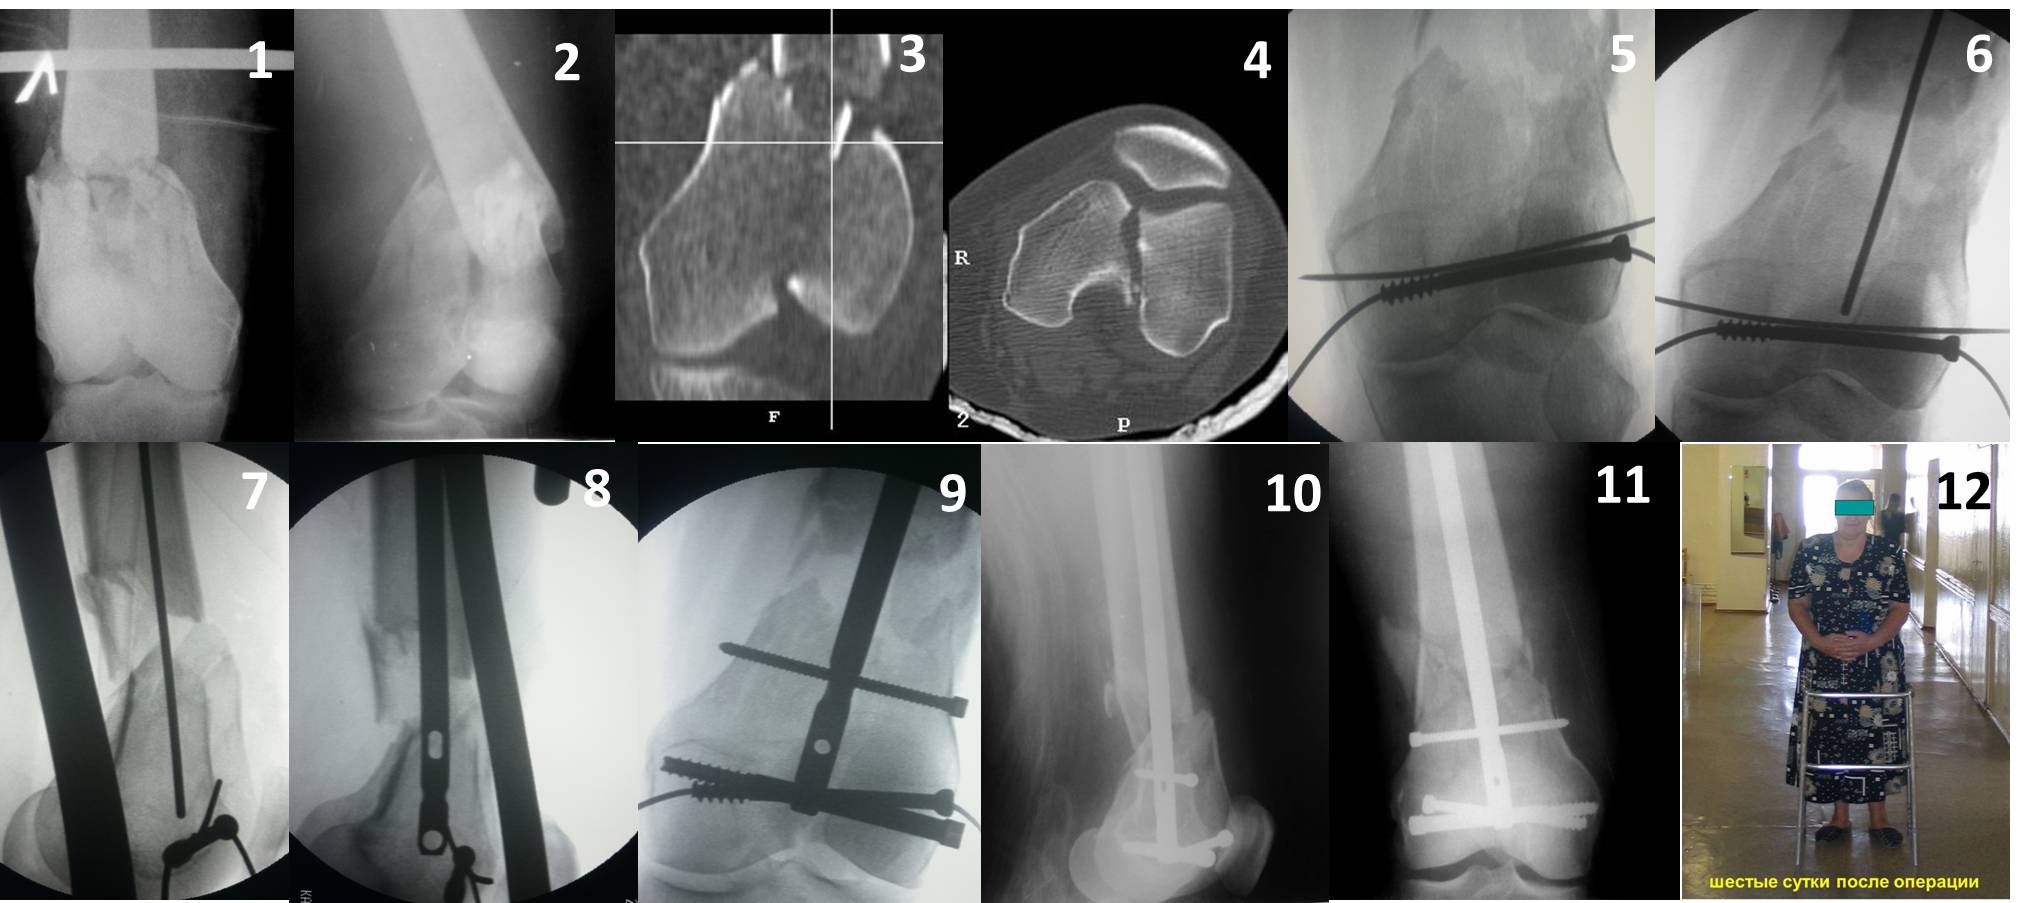

Ну зачем же так. Всё-таки считается "золотым стандартом". Во вложенном файле коллаж из сохранившихся фотографий одной из операций. Всё сделано закрыто и без ЭОПа.

Ответ на эту часть Вашего поста – вложенный файл. Больная оперирована неделю назад по поводу открытого перелома дистального эпиметафиза бедренной кости. После операции она идёт в рентгенкабинет для выполнения послеоперационной контрольной рентгенографии, представленной на слайдах 10 и 11. Узнав, почему её фотографируют, просила передать Вам, Антон, привет.

Коллеги, извиняюсь за задержку с результатом. Через медиальную артротомию обнажили н/3 бедра, отрепонировали внутренний мыщелок, затем по нему сопоставили суставную поверхность бедра с латеральным мыщелком.

Больная выписана в ортезе с регулируемым углом сгибания в колене, с рекомендациями через 3 нед. удалить спицы и начать разрабатывать сустав.

По прямому снимку репозиция удалось, поздравляю! А с латеральной стороны подозрение на флексионный компонент латерального мыщелка остается, а снимок получился косым, надо было бы повторить.

Выбор имплантов не совсем удачный, подкожно выступающие болты в мыщелках вскоре могут привести к проблемам. Вместо солитарной фиксации болтом-стяжкой дистально можно было бы добавить пару винтов, которые создали бы ротационную стабильность и межфрагментарную компрессию.

Возможно, есть скрытый замысел, неочевидный для нас - не понятны латерально оставленные спицы. Спицы возможный очаг вторичного осложнения, и, тем более у взрослых, тонкие спицы не создают адекватную фиксацию.

Djoldas,скрытого смысла в спицах нет. Без них латеральный мыщелок получается фиксированным только к медиальному, который, в свою очередь, фиксирован к проксимальному отломку. Соответственно латеральный мыщелок не фиксирован к бедру. Спицами мы попытались создать какую-никакую-стабильность латерального мыщелка относительно проксимального отломка бедра.

Болт-стяжка, на мой взгляд, создает не меньшую межфрагментарную компрессию чем винты. Не понял относительно ротационной стабильности винтов.